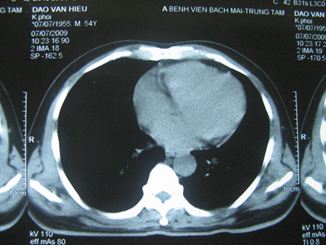

Chụp cắt lớp vi tính lồng ngực: Khối u thuỳ giữa phổi phải kích thước 26 ´ 13mm, không có hạch rốn phổi, trung thất.

Chụp cắt lớp vi tính lồng ngực

Trước điều trị: Hình ảnh khối u thuỳ phổi phải, kích thước 26x13mm

Sau điều trị: Không còn khối u, không có hạch trung thất